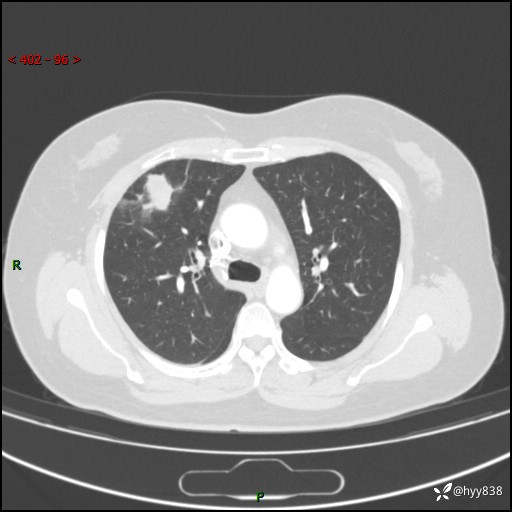

现病史:患者于2天余前无明显出现间断胸痛,无头痛、头晕,无心慌、胸闷、胸痛、呼吸困难、低热、盗汗,无腹痛、腹胀等不适,未进行进一步诊治。于2024.04.14在当地市人民医院行胸部CT检查提示:右肺上叶胸膜下结节。现患者为求进一步诊治,来我院就诊。以“肺肿物”收入我科。 患者自起病以来,精神可,睡眠可,饮食可,大小便正常,体重无明显改变。

胸部CT增强(肺窗,外院平扫)